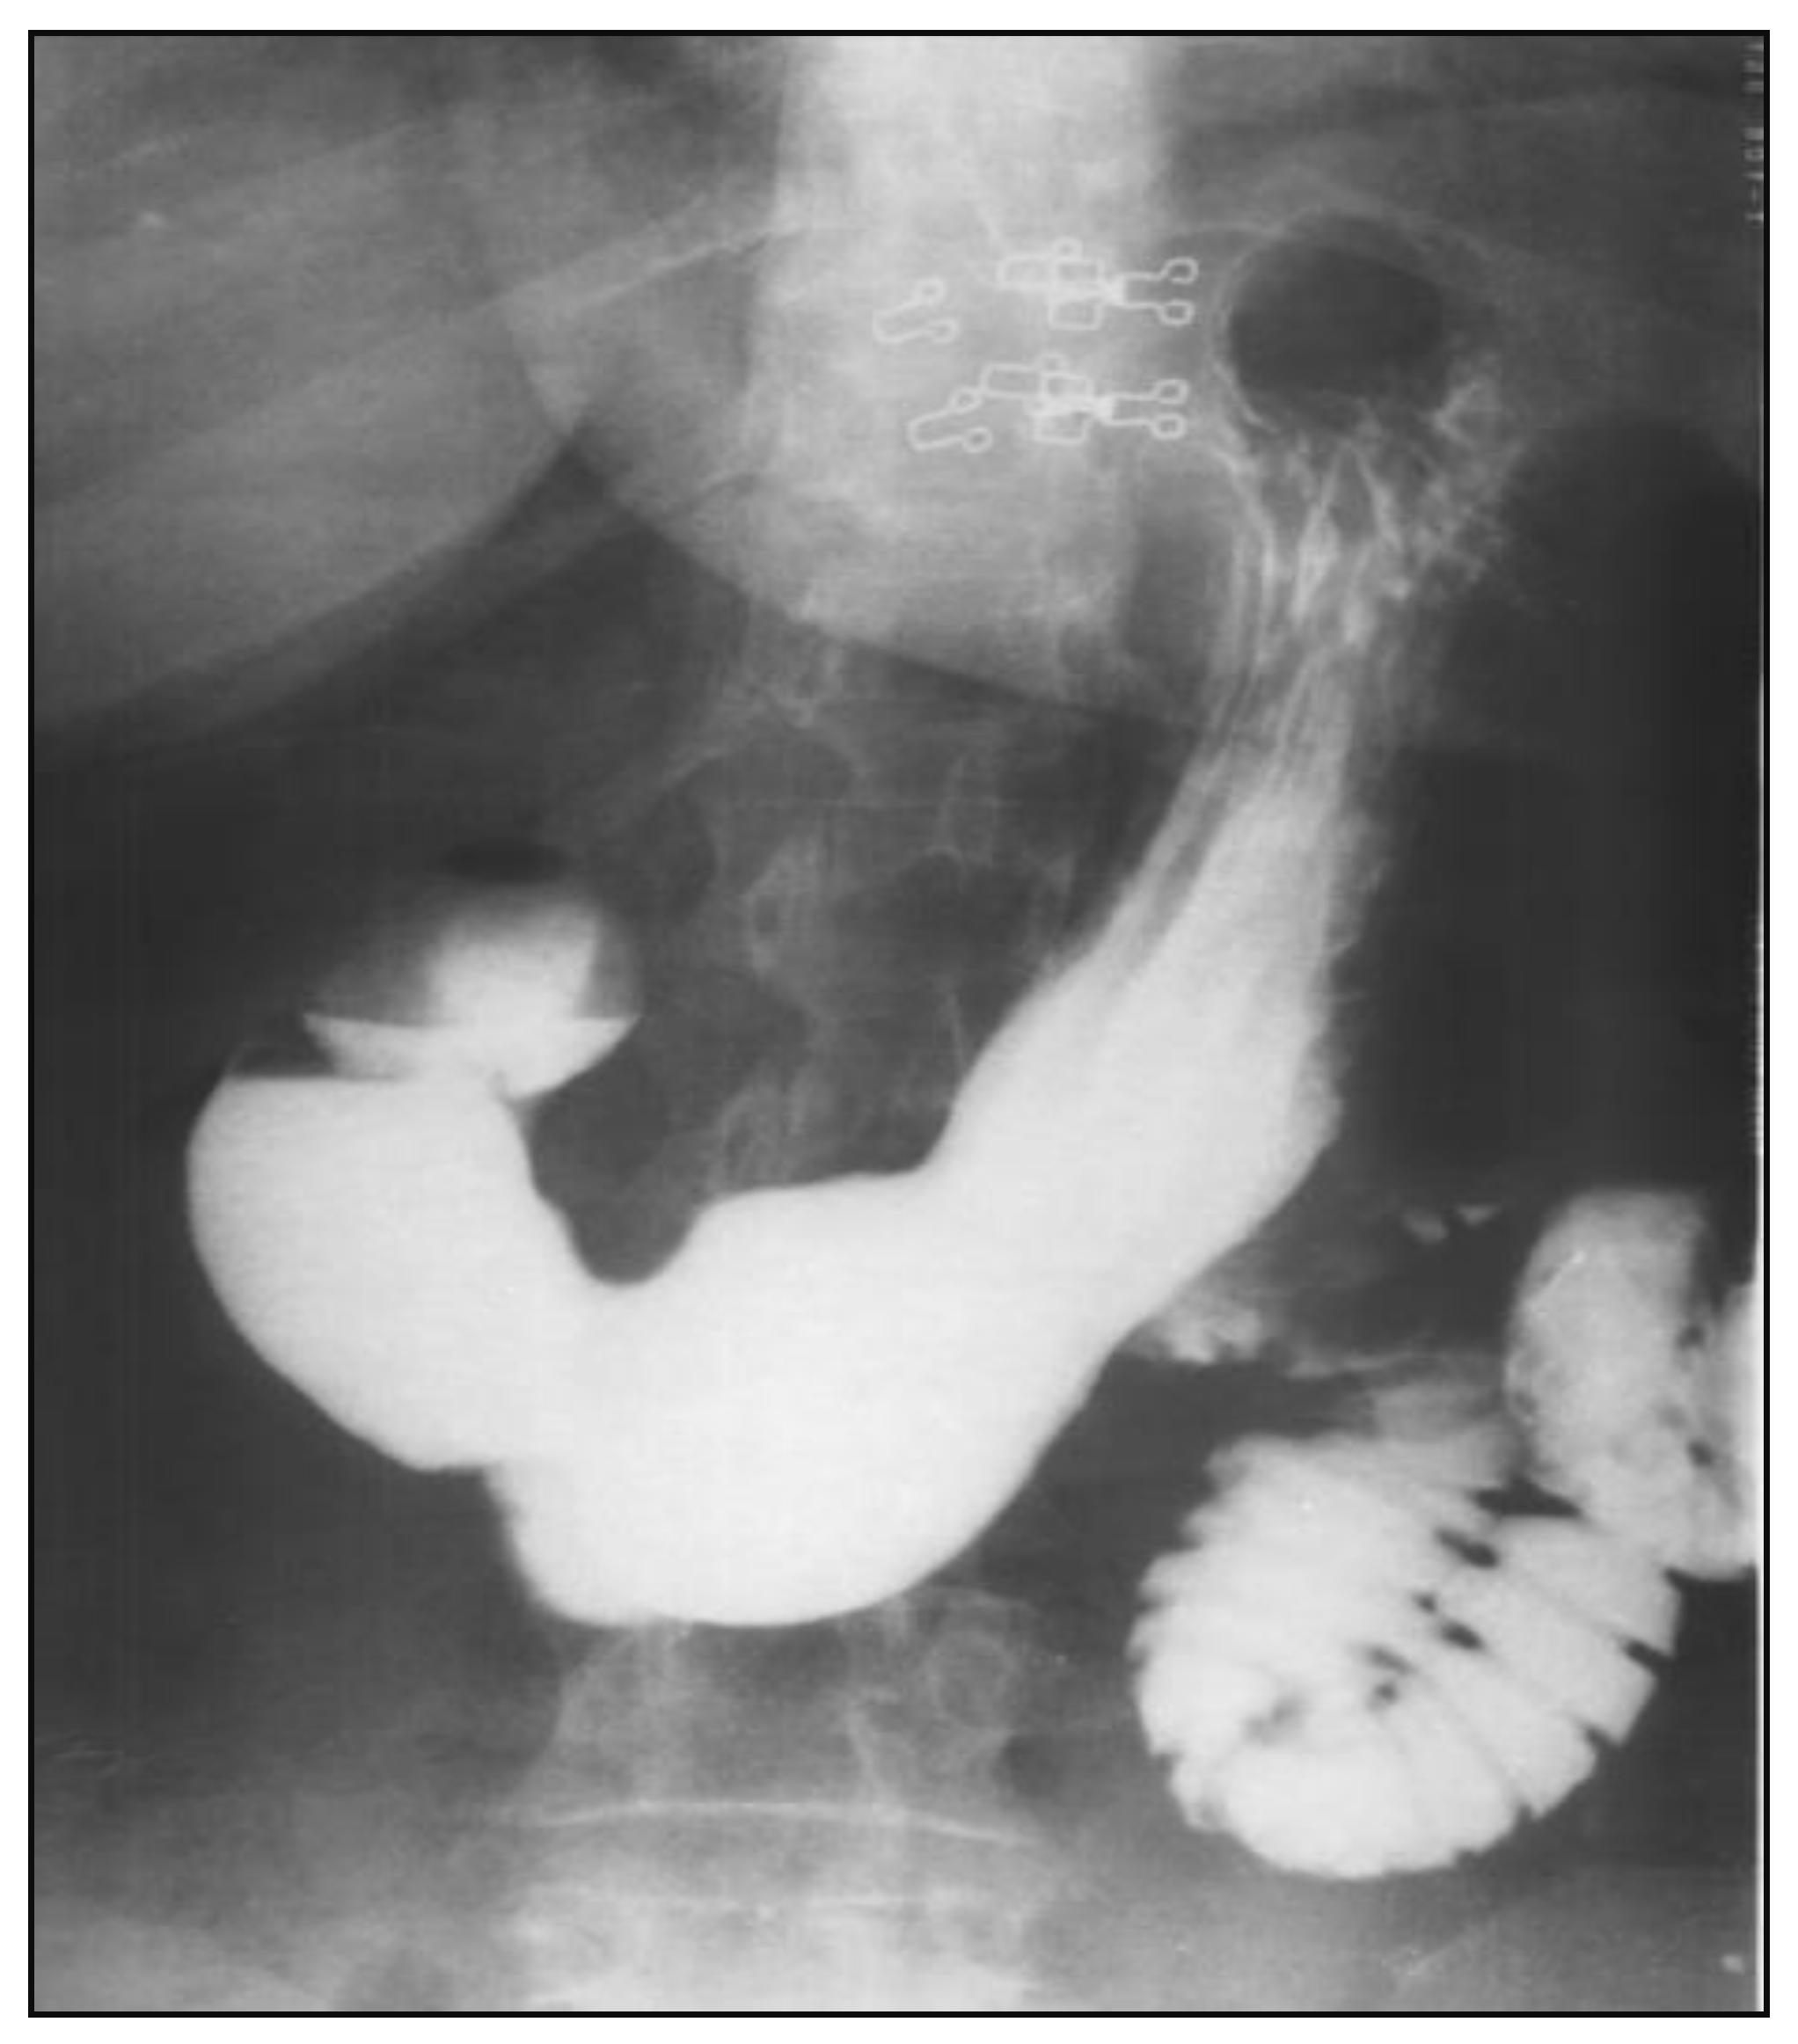

After nasogastric tube positioning, the upper endoscopy revealed dilated hypotonic stomach and duodenum with lesions of erosive gastritis and duodenitis. Using barium study of the upper gastrointestinal tract, we found a filling defect of the fourth portion of the duodenum, with dilated stomach and duodenum proximal to the site of obstruction; we also found gastroesophageal reflux without radiological signs of hiatal hernia (Figure 1). Ultrasonography and CT scan showed no metastases.

Figure 1.

Barium study of the upper gastrointestinal tract filling defect of the fourth portion of the duodenum with dilated stomach and duodenum proximal to the site of obstruction and gastroesophageal reflux without radiological signs of hiatal hernia.